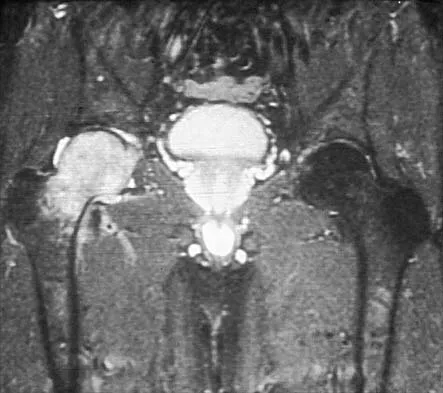

Question 47

A 46-year-old woman has bilateral groin pain, with more severe pain on the left side than on the right side. Figures 44a and 44b show a radiograph and a T1-weighted MRI scan. What is the most likely diagnosis?

Explanation

Question 48